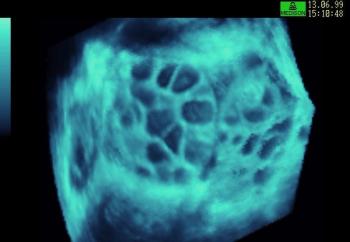

4D image of 29 weeks pregnancy, multiple anomalies: Clinch hand, omphalocoele, single atrium